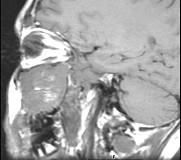

问题 15岁,男性,渐进性鼻塞1年余,MRI扫描如图所示,请选择最可能诊断()

选项 A.鼻咽部纤维血管瘤 B.鼻咽部脓肿 C.脊索瘤 D.鼻咽部囊肿 E.鼻咽癌

答案 A